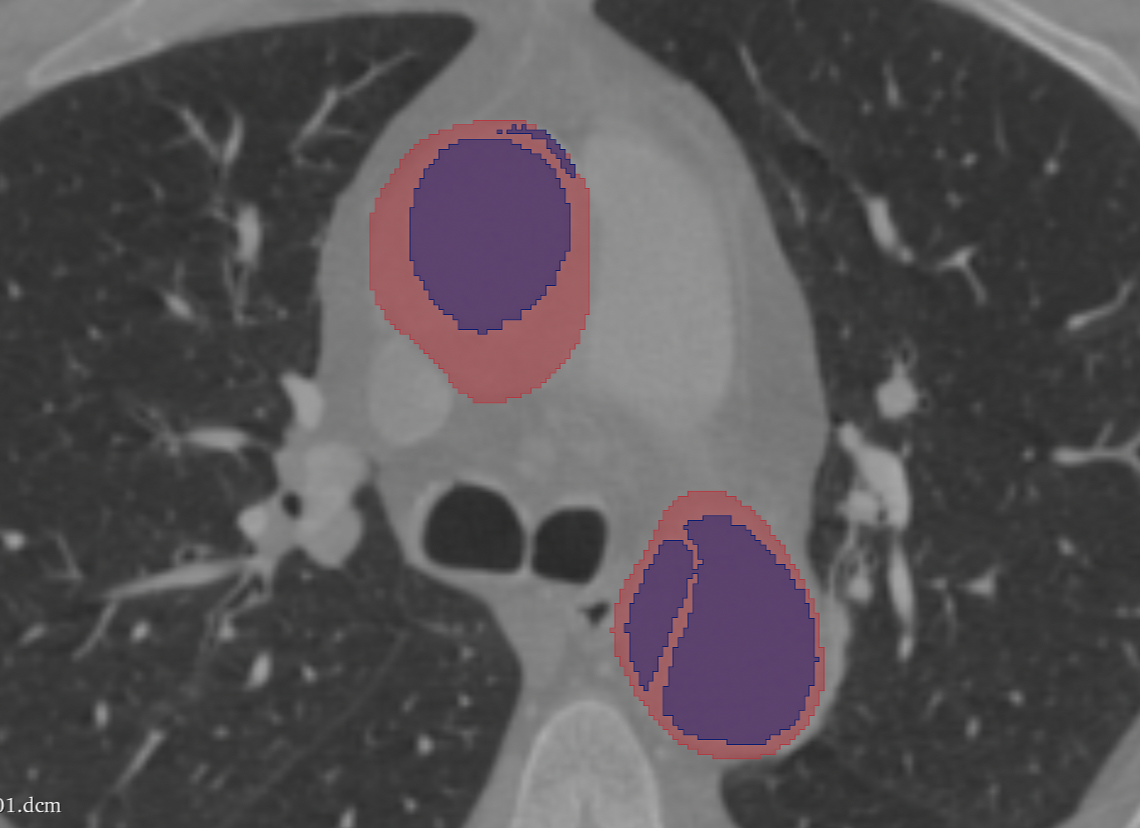

Welcome to our comprehensive cardiology annotation services. Our team of experienced medical professionals and advanced technology combine to provide accurate and detailed annotations for cardiology imaging data. From EKGs to echocardiograms, we offer precise and reliable annotations to support research, diagnosis, and treatment planning. Whether you're in need of precise measurements, feature detection, or anomaly identification, our services are tailored to meet your specific needs. Trust us to deliver high-quality, efficient, and insightful annotations for your cardiology data.